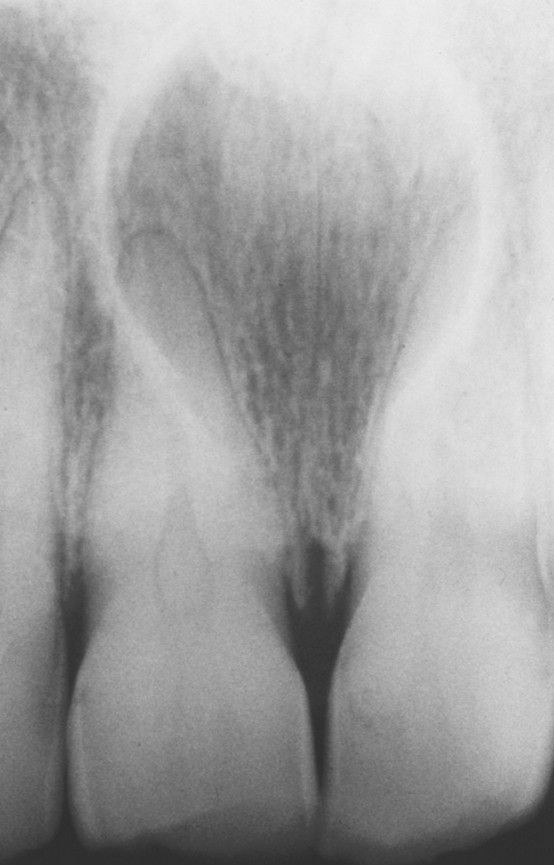

Nasopalatine duct cyst

Well-circumscribed radiolucency between and apical to the roots of the maxillary central incisors.